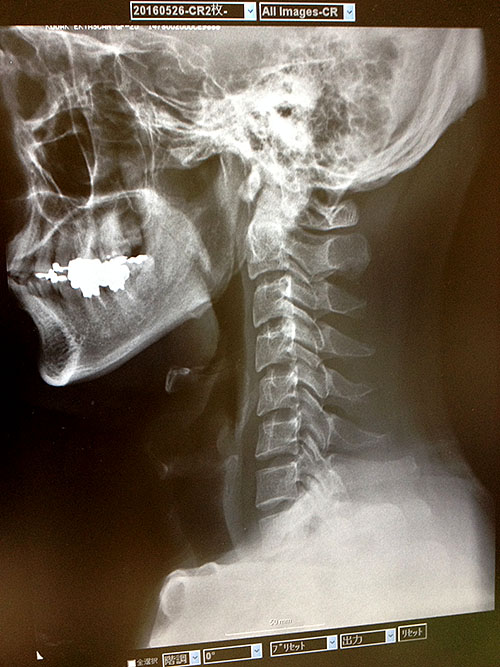

変形性頚椎症|京都府京田辺市 川東整形外科/整形外科 ...

変形性頚椎症|京都府京田辺市 川東整形外科/整形外科 ... from www.kawahigashi-seikei.com